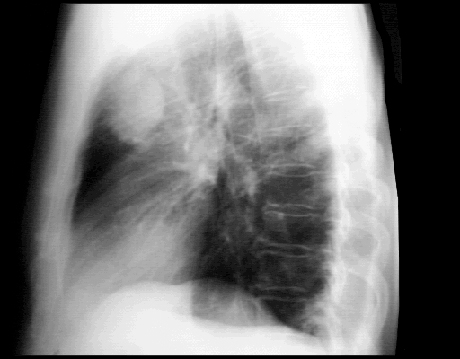

These chest X rays show a pulmonary lesion, or mass. In this PA view, a solitary lesion is seen in the right upper lobe. The mass shows no cavitation or calcification and should be considered cancerous unless proven otherwise. There is also asymmetry of the lung apices with pleural thickening and stranding on the right. This may be due to radiation or previous granulomatous disease such as tuberculosis. Tha cardiovascular structures are unremarkable. The lateral view also demonstrates the solitary lesion or mass in the peripheral portion of the anterior segment of the right upper lobe, with pleural thickening and stranding in the apex. The cardiovascular structures are, again, within normal limits.